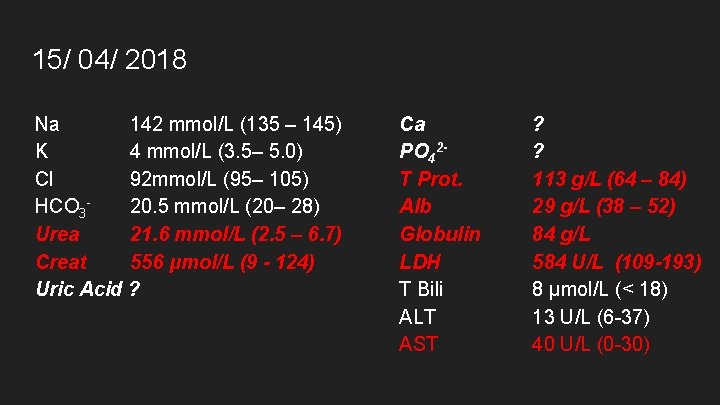

15/ 04/ 2018 Na 142 mmol/L (135 – 145) K 4 mmol/L (3. 5– 5. 0) Cl 92 mmol/L (95– 105) HCO 320. 5 mmol/L (20– 28) Urea 21. 6 mmol/L (2. 5 – 6. 7) Creat 556 μmol/L (9 - 124) Uric Acid ? Ca PO 42 T Prot. Alb Globulin LDH T Bili ALT AST ? ? 113 g/L (64 – 84) 29 g/L (38 – 52) 84 g/L 584 U/L (109 -193) 8 μmol/L (< 18) 13 U/L (6 -37) 40 U/L (0 -30)